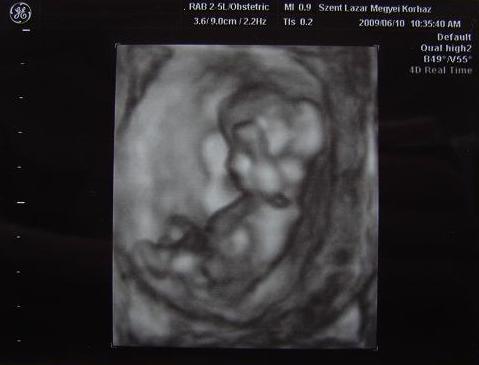

:) ha lesz idod, irj le reszleteket is a vizsgalat eredmenyeirol, mit latott a doki...!